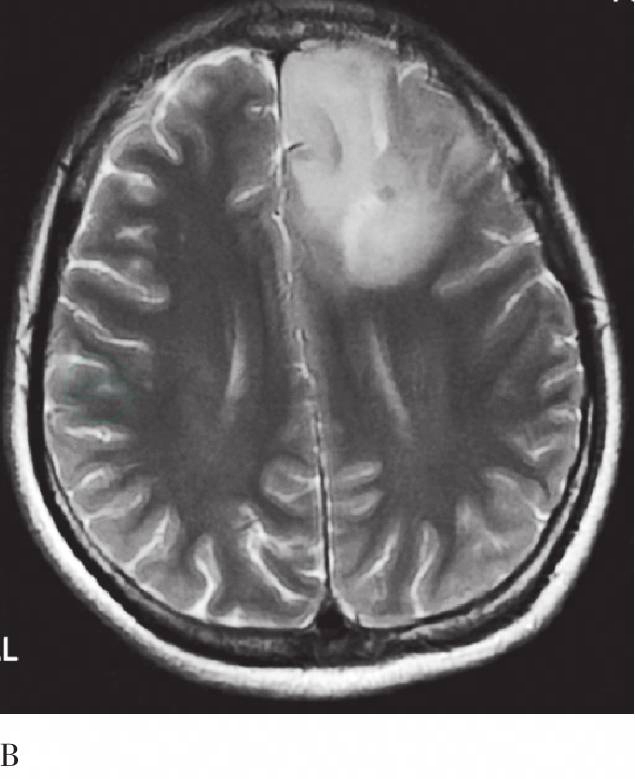

图4 头MRI平扫及增强横断层图

A. 左额病变T1WI;B. 同A层面T2WI;C. 同A层面增强;D. 右颞病变T1WI;E. 同D层面T2WI;F. 同D层面增强。MRI示左额不规则稍长T1、稍长T2信号肿块影,增强未见明显强化;右颞局部皮层增厚,可见团块状稍长T1、长T2信号影,增强未见明显强化

其他影像学图像表现:头MRI平扫示左额不规则混杂信号肿块影,边界不清,呈稍长T1、稍长T2信号,其内可见片状长T1、长T2信号影,左侧侧脑室前角受压变形,大脑镰前部向右侧移位。右侧颞叶局部皮质增厚,可见团块状稍长T1、长T2信号影,累及皮质下白质,邻近脑质受压内移。MRI增强左额及右颞病变均未见明显强化,考虑多中心胶质瘤。